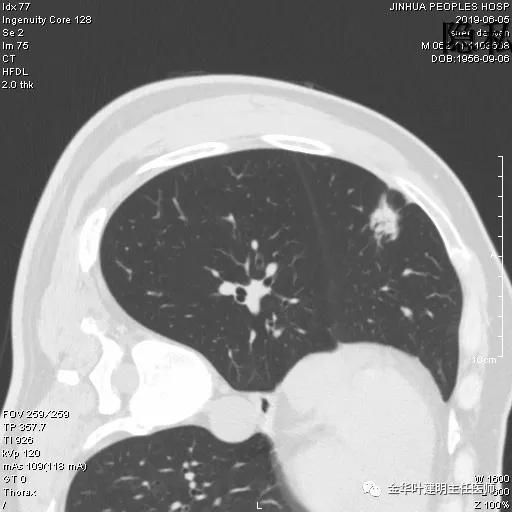

金华的申某,今年62岁,前段时间感冒了咳嗽,长时间不好,在家人的一再要求和坚持下,终于同意来到人民医院检查治疗,住到了呼吸内科,检查胸部CT居然发现其右肺中叶有个结节,如下图:

可见右中叶结节,密度欠均匀,似有毛刺及胸膜牵拉,考虑恶性可能大,遂予以再行靶扫描,如下图:

典型的恶性征象,胸膜牵拉凹陷、血管集束征、密度不均、支气管通气征、边缘磨玻璃成分等征象都有。让我去会诊,到了床边,怎么感觉这病人这么面熟呢右肺中叶在哪?他早于我就叫来了:“叶医生好,我是叶某的老公呀,她几年前肺癌在你这里开刀的。”哦,难怪了,叶某术后还每半年回门诊来复查的,都是申某陪来的,对老伴很好的一个人。我找出了叶某2015年手术时的CT片,我们来瞧瞧: